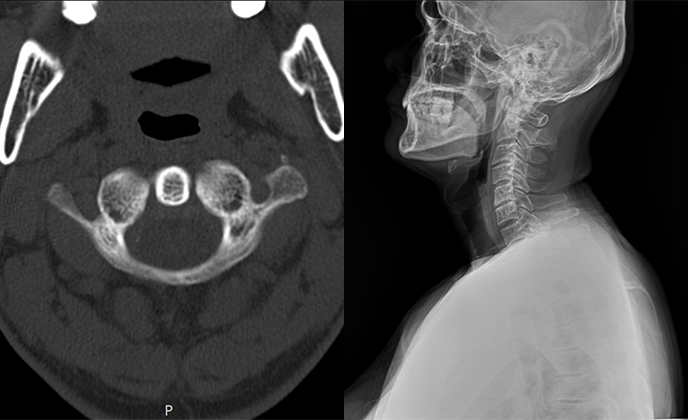

▲ 정상체혈판

▲ 치료 전 (2016년 1월 21일)

▲ CTA 5개월 착용 (2016년 6월 29일)

▲ CTA 9개월 착용 (2016년 10월 29일)